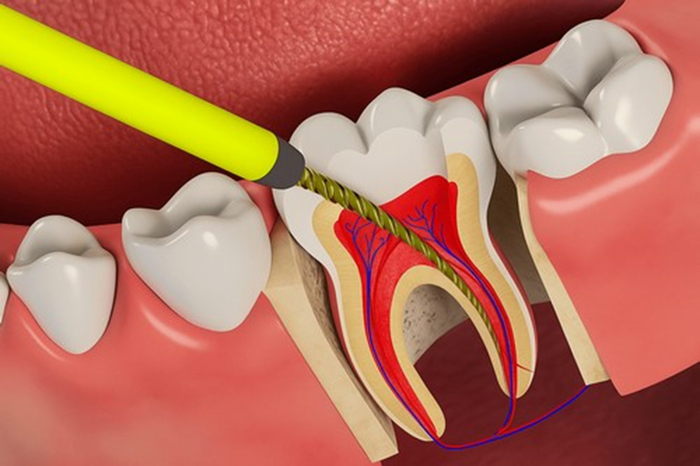

6) Расширяем каналы.

Специальными сверлами, хотя правильно они называются файлами.

Задача расширения канала- это убрать инфицированные ткани и обеспечить условия для отмывания канала антисептиками. Это примерно, как бомбежка.

7) Промываем каналы

В этом как раз и кроется главный принцип лечения. Как сказал дедушка Шильдер в прошлом веке: «Не так важно, чем мы канал запломбируем, как важно то, что мы из него достанем.»

От того как мы отмоем канал и будет зависеть вероятность успеха любого лечения

На данный момент сейчас почти все моют каналы из специального шприца 3% гипохлоритом натрия, так как он уничтожает всю органику напрочь, улетучивается, не оказывая какого-либо негативного влияния на организм. Лить нужно его не жалея, от души, периодически взбивая в канале ультразвуком, чтобы он более активно омывал все стенки, вымывая органику из мелких ответвлений.

Также мы добавляем ещё и этилендиаминтетрауксусную кислоту, которая откупоривает дентинные канальцы, позволяя при повторной отмывке гипохлоритом выжечь как можно больше заразы. А ещё гипохлорит можно активировать ультразвуком.